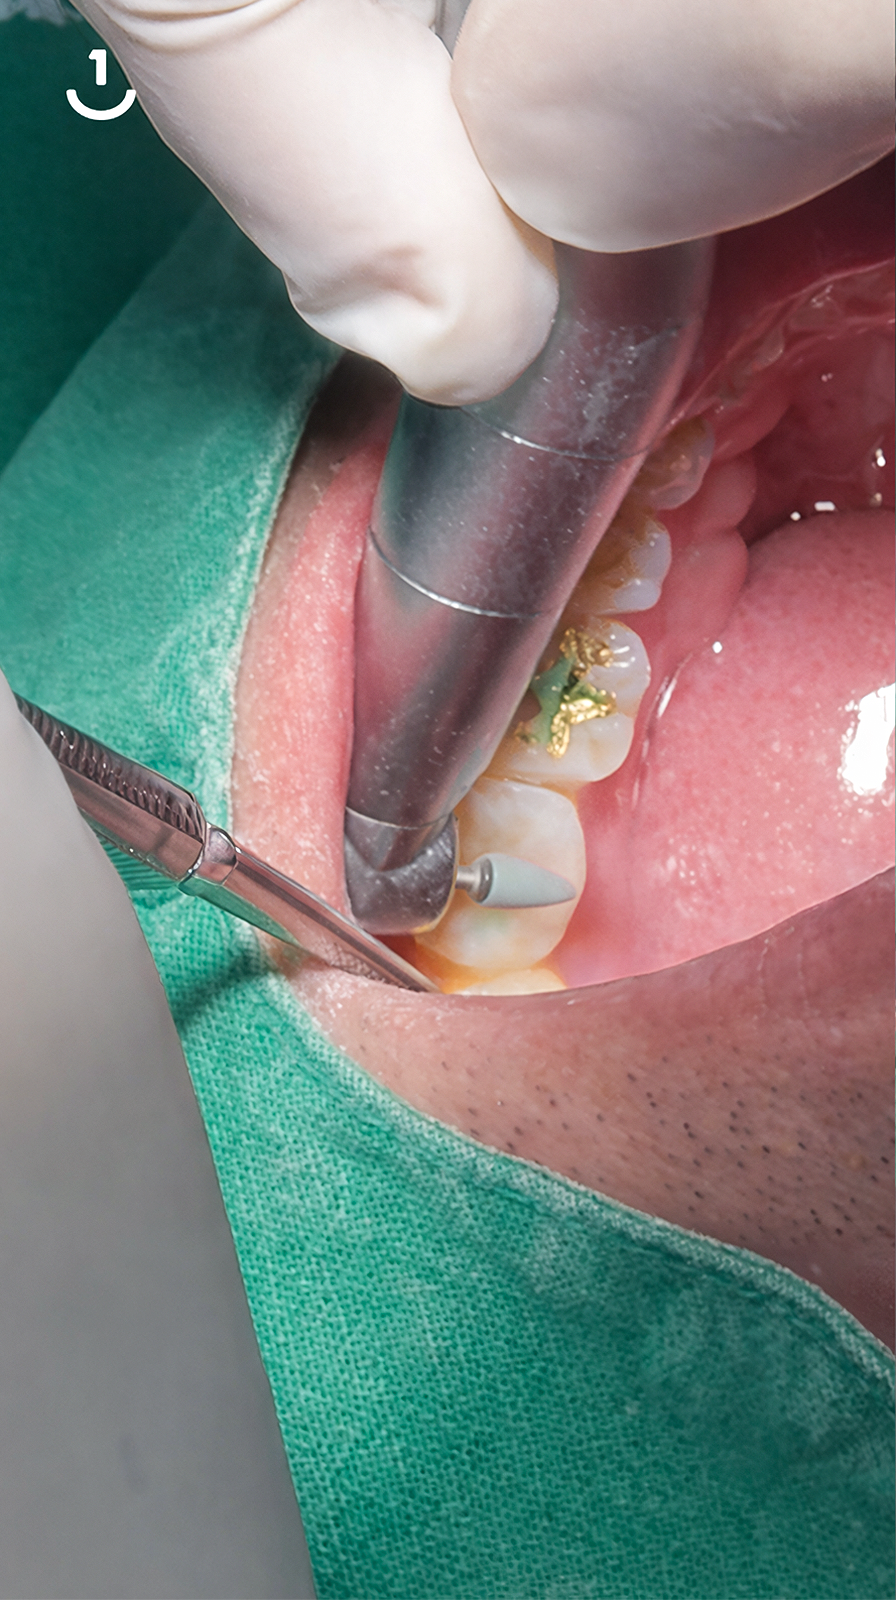

01

충치 제거

02

아쿠아케어 진행

03

큐레이뷰로 충치 및 잔여물 확인

04

적합 맞추기

05

에칭 과정

06

프라이머 도포 후 본딩 도포

07

본딩제 광중합

08

레진 베이스로 기틀 만들기

(물렁한 레진 사용)

09

강화섬유를 적용시키는 과정

10

레진빌드업시작

(딱딱한 레진 사용)

11

수용성 바세린으로

레진 경도와 강도 강화

12

교합 조정 과정

13

팔리싱 과정

14

레진빌드업 치료 후

※ 본 이미지는 시술 과정 이해를 위해 생성된 이미지로, 실제 시술 장면을 직접 촬영·노출한 것이 아닙니다.